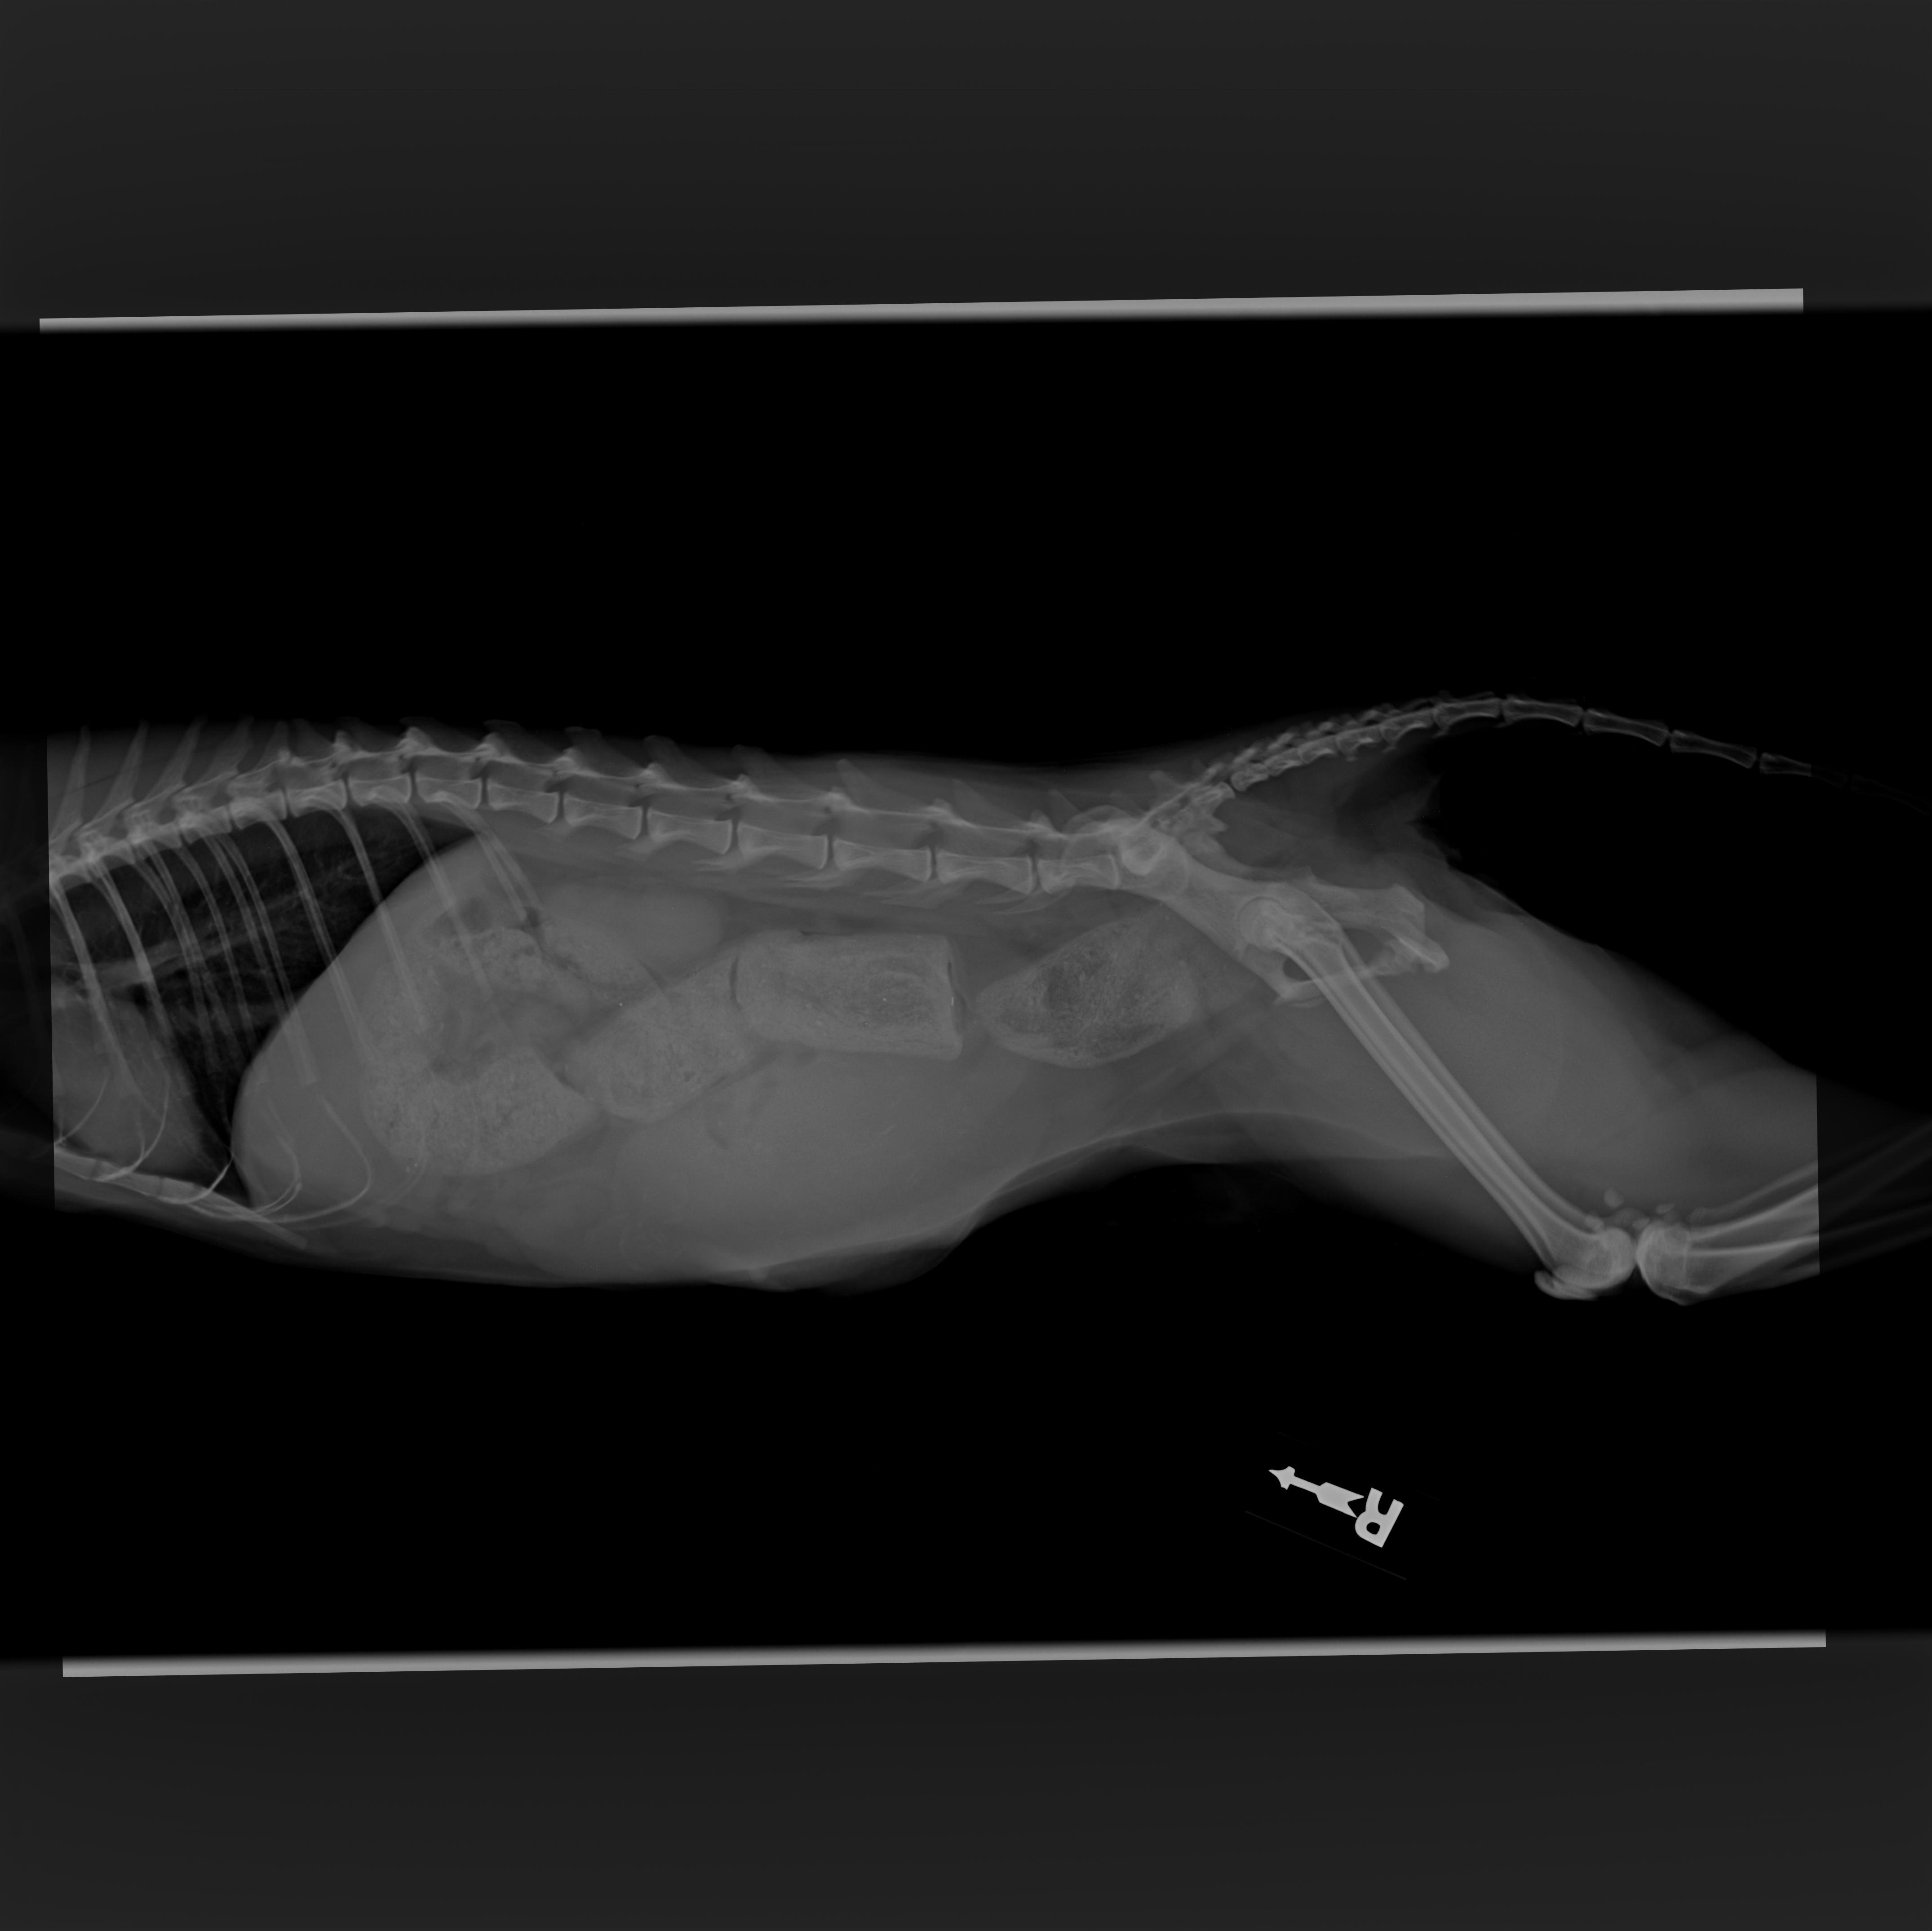

During the first vet visit I had asked if she might be pregnant, and noticed she walked strangely to which the first vet told me she was perfectly healthy and was not likely pregnant. Upon seeing another doctor and emergency vet, it's been uncovered that she was hit by a car, pregnant with three kittens, and severely constipated (this has now turned into obstipation as I type)

The car hitting her has caused her pelvis bones to break in a way that's causing her to be constipated/obstipation and is posing a danger to not only herself but her three kittens, as she is unable to defecate or give birth to these kittens.

I received the call this morning around 9:30AM on August 1st 2025 after two long visits to the emergency vet and was notified that they would need to perform surgery to relieve her constipation / manually extract obstipation, save or remove her uterus and babies, and potentially amputate her leg. The quote I was given was anywhere between $8k - 13k, increased up to over 20k based on any complications (amputation, c section, medication) . I'm attempting to take out a loan that I'm unsure will get approved for and I'm currently using Scratchpay to support her, but I have run out of options. Scratchpay has only granted me $8k, all donations will go towards the rest of her bill as needed to save her life.